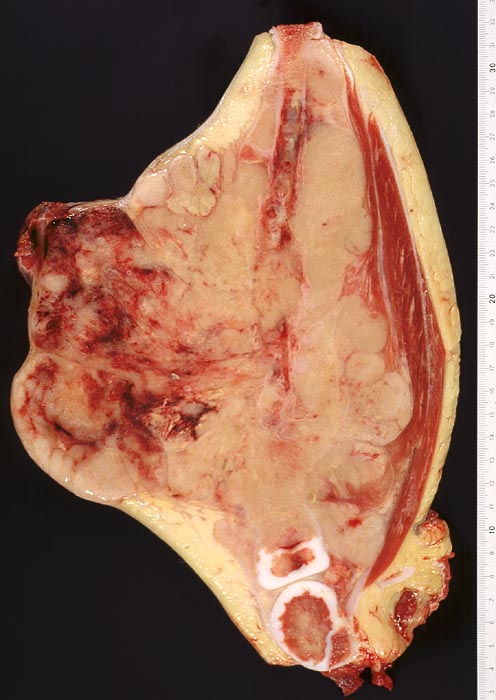

Meist entstehen Ewing Sarkome primär im Knochen. Es kommen aber auch extraskelettale Formen vor. Prinzipiell können alle Skelettabschnitte betroffen sein. Bevorzugt befallen sind aber die langen Röhrenknochen (diaphysär), das Stammskelett, der Schädel, die Rippen und der Beckengürtel. Extraskelettale Ewing Sarkome liegen am häufigsten paravertebral oder in der Brustwand, seltener in anderen Weichteilen.

Die Tumoren sind makroskopisch grauweiss und wachsen destruktiv und infiltrativ. Nekrosen und Einblutungen sind häufig. Histologisch lassen sich solide Rasen monomorpher, kleiner, rundlicher Tumorzellen mit dichtem Chromatin und wenig Zytoplasma nachweisen (sog. small-blue-round cells). Metastasen treten vor allem in der Lunge und in anderen Skelettabschnitten auf. Die Differentialdiagnose klein-blau- und rundzelliger Tumoren im Kindesalter ist breit. Kleinzellige Osteosarkome, Neuroblastome, Lymphome und mesenchymale Chondrosarkome können ein histologisch ähnliches Bild zeigen, speziell in kleinen Biopsien, und müssen mit Hilfe von (molekularen) Zusatzuntersuchungen und unter Einbezug klinischer und radiologischer Befunde voneinander abgegrenzt werden.